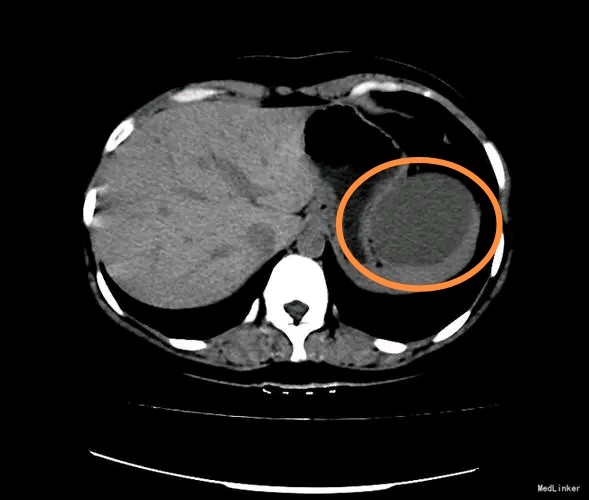

相对于肝囊肿,脾脏囊肿少见得多。但无论如何,囊肿一般都是水泡,良性,没有恶变风险。类似肝囊肿一样处理,只要不是太大或生长太快,都可以观察。

偶尔为复杂囊肿,复杂囊肿如果考虑恶性(囊腺癌)或者不能排除恶性,需要像恶性肿瘤一样及时手术切除,当然,囊腺癌发病率极低,一般患者勿需担心。还有些囊肿,虽然不是恶性,但可能继发出血、感染等,内含黑褐色浑浊腐臭的液体或糊状成分,可能有发热、疼痛等不适,亦需要尽早处理。

绝大多数囊肿属于单纯囊肿,就是小水泡。一般是先天或后天自然生长出来的,就像皮肤上面的痣,确切成因不明。

小囊肿即不会有不适的症状,也不会有什么危害,更不会癌变。即不需要手术,更不需要吃药(吃药无效;吃药无效;吃药无效;重要的事情说三遍)。

但是,亦有部分单纯囊肿建议手术:第一,囊肿巨大,比如超过10公分。肯定是进行性增大的囊肿;第二,生长过快的囊肿,比如每年直径增加1-2cm甚至更多,这种囊肿可以短短几年内超过10cm;第三,考虑囊肿是引起不适的主要原因,比如大囊肿可以压迫胃,引起腹胀、进食减少甚至营养不良。这类囊肿往往不小,小囊肿,无论长在哪里,都不可能有不适。